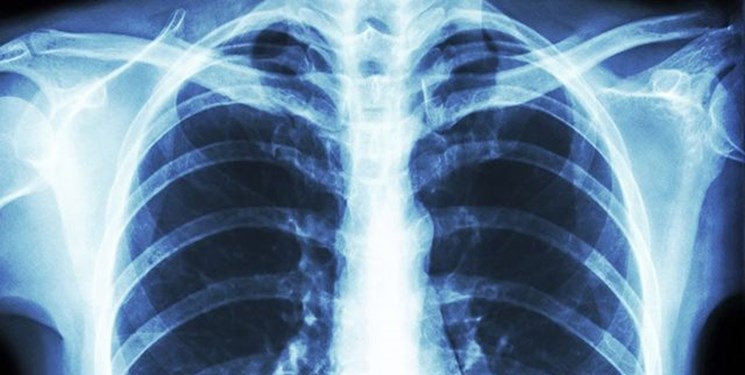

مردانی ورزش های هوازی ریوی برای بهبود اکسیژیناسیون و تقویت ریه افراد مبتلا به کرونا را مفید دانست و گفت: حتی موقعیت ها و حرکاتی که در تصاویر و فیلم ها آموزش داده می شود برای بهبود مبتلایان به کرونا می تواند کمک کننده باشد و زودتر بهبود می یابند.

وی توصیه ای هم برای افراد سالم داشت: افراد سالم می توانند برای پیشگیری از بیماری و تقویت ریه هایشان نفس عمیق بشکند. همچنین ورزش های صبحگاهی به منظور تقویت ریه بسیار خوب است.